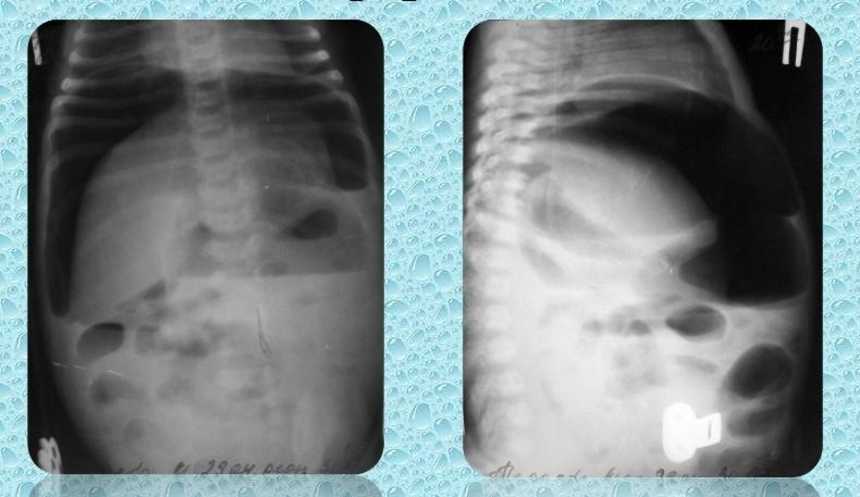

Легочную форму муковисцидоза диагностируют с помощью рентген-исследования органов грудной клетки и бронхоскопии. При рентген-исследовании выявляют эмфизему легких, ателектазы, перибронхиальный и инфильтративный склероз легких. При бронхоскопии в просвете бронхов обнаруживают вязкую нитеобразную мокроту.

Мекониевая непроходимость

Муковисцидоз, классифицированный в такой форме как мекониевая непроходимость, диагностируется у 35 % детей в первые дни жизни, реже в более позднем возрасте. При данной форме муковисцидоза отсутствует фермент трипсин, который расщепляет белки и пептиды. Поэтому в первый-второй день у детей не выделяется первородный кал (меконий). Кишечная непроходимость сопровождается у младенцев беспокойством, вздутием живота, рвотой с желчью, срыгиваниями. Спустя 1-2 дня у детей с кистозным фиброзом этой формы наблюдается одышка, бледность и сухость кожного покрова, дегидратация, интоксикация, возникают сосудистые сетки на теле.